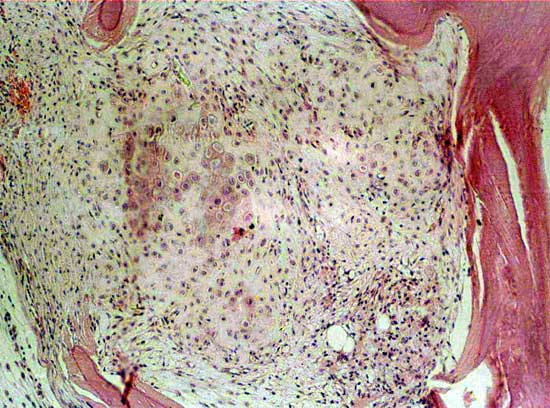

1. 兔骨髓基质细胞能够在培养条件下形成集落并持续扩增,其中部分集落碱性磷酸酶表达阳性,细胞接近汇合时有近半数细胞有ALP活性表达;汇合后能够形成钙化小结;G-CSF虽能够增加骨髓中有核细胞数量,但克隆形成率并未有明显增加。

骨髓有核细胞100X                      骨髓有核细胞100X